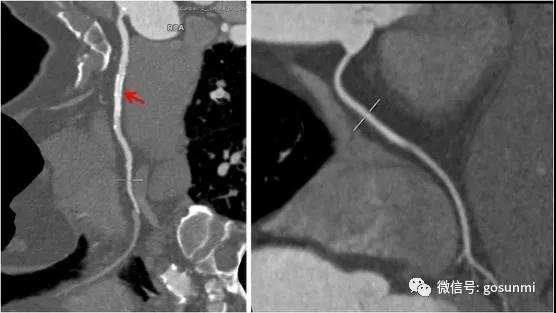

對(duì)于冠心病行冠脈支架植入術(shù)后的患者來(lái)說(shuō),也可以通過(guò)冠脈CTA檢查來(lái)觀(guān)察與評(píng)估支架的通暢情況等。如下圖所示,左圖顯示右冠的支架通暢,右側(cè)為正常右冠。